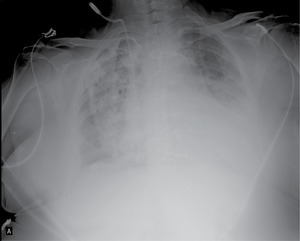

Bezpośrednio po zabiegu wykonano RTG klatki piersiowej (ryc. 1A).

1. Jakie rozpoznanie jest najbardziej prawdopodobne na podstawie zdjęcia RTG (RYC. 1A)?

a. Zapalenie płuca prawego

b. Zapalenie płuca prawego z płynem po stronie lewej

c. Odma opłucnowa płuca prawego

d. Zmiany opłucnowe po przebyciu gruźlicy w płucu prawym z płynem w lewej jamie opłucnowej

Obraz widoczny na zdjęciu wykonanym bezpośrednio po wyjeździe z sali operacyjnej na oddziale pooperacyjnym sugerował odmę prawostronną, która dyżurnemu kardiochirurgowi i anestezjologowi wydawała się na tyle istotna, że należało ją zdrenować. Jednak ze względu na bardzo znaczną otyłość pacjentki, a przy tym brak jakichkolwiek problemów z wentylacją po konsultacji z kardiochirurgiem operującym nie założono drenu.

Na zdjęciu rentgenowskim A-P widzimy tylko 50% miąższu płucnego! Jeśli chcą Państwo ocenić cały miąższ płucny, należy zlecić zawsze dwie projekcje – A-P oraz boczną.